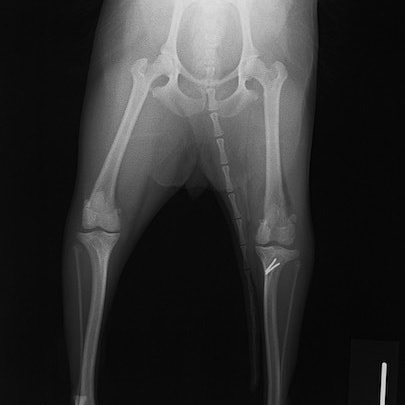

■ 症例24 キャバリア 7か月

左右膝蓋骨内方脱臼(左:グレードⅣ 右:グレードⅢ)

以前から左右後肢の跛行が認められ、整形外科学的検査・レントゲン検査により左右の膝蓋骨脱臼が認められた。症状が重度である左膝の膝蓋骨脱臼整復術を行った。外科手技は縫工筋及び内側広筋の解放、脛骨粗面の外側転位、滑車ブロック形造溝術、内外側関節方の縫縮を実施した。術後一か月時点で、左の膝蓋骨は安定しており経過は良好である。

本症例は成長期における重度の膝蓋骨脱臼であり、術後の再発の可能性もあるため、経過をしっかりと観察していく必要がある。また、今回手術を実施していない右膝に関しても経過を観察し、手術を検討していくこととする。